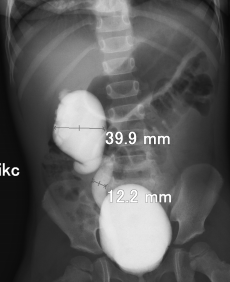

Рефлюксирующий мегауретер: Визуализация и медицинские изображения

Раздел: Фотопуть к знанию